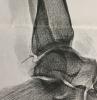

Объектами исследования выступал комплекс документарных материалов, имеющих решающее значение для оценки качества оказанных медицинских услуг. Эти материалы были представлены в бумажном виде и на рентгеновской плёнке, их состояние было признано удовлетворительным для проведения анализа. Комплект включал в себя как оригиналы, так и копии документов, содержащие как рукописные, так и печатные записи.

• Рентгеновские снимки (2 шт.).

В процессе работы экспертов были применены методы тщательного анализа и сопоставления данных, полученных из различных источников. Производилось детальное изучение медицинских карт и рентгеновских снимков, а также всех представленных в деле документов. Были использованы цитирование ключевых фрагментов и сравнительный анализ полученных сведений со стандартами, регламентированными федеральными законами, постановлениями и приказами Министерства здравоохранения Российской Федерации, включая Федеральный закон от 31.05.2001 №73-ФЗ «О государственной судебно-экспертной деятельности в Российской Федерации», Федеральный закон от 21.11.2011 №323-ФЗ «Об основах охраны здоровья граждан в Российской Федерации», Постановление Правительства РФ от 17.08.2007 №522 «Об утверждении Правил определения степени тяжести вреда, причиненного здоровью человека», а также Приказы Минздрава России от 10.05.2017 №203н, устанавливающий критерии оценки качества медицинской помощи, и от 12.11.2012 №901н, регламентирующий порядок оказания медицинской помощи по профилю «травматология и ортопедия». Все эти меры позволили экспертам сформулировать обоснованные ответы на поставленные перед ними вопросы с использованием принципов формальной логики.